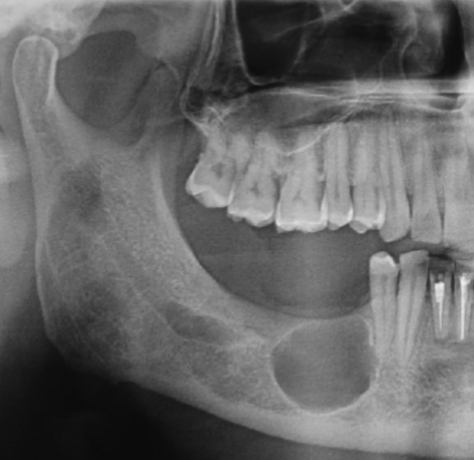

What is the Green Dot?

Submandibular Fossa

What is the Purple Dot?

Radicular Cyst

What is the dental anomaly?